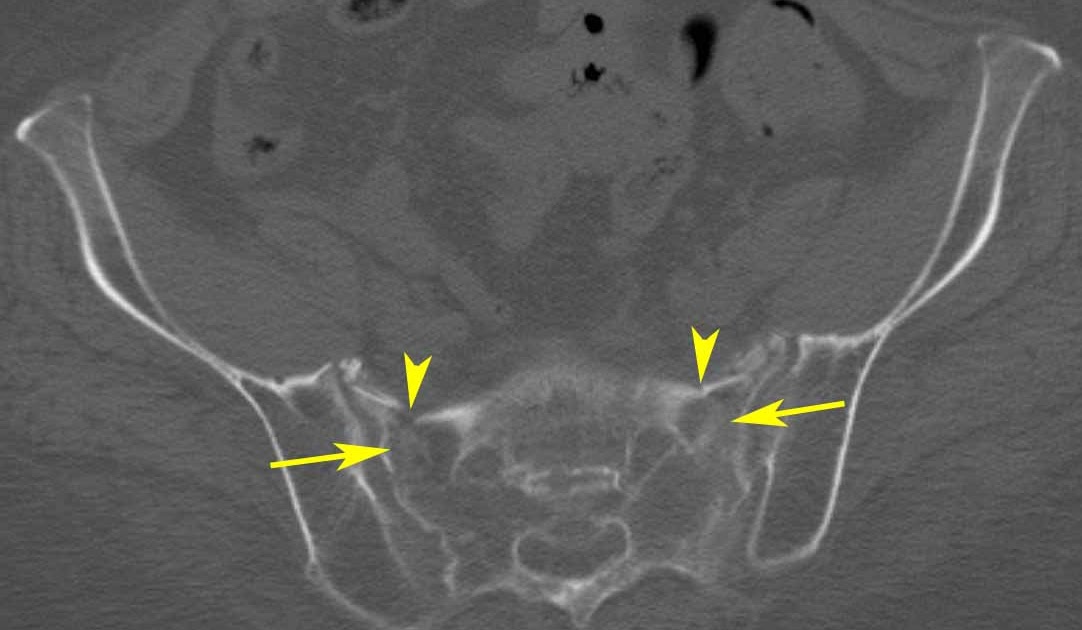

The pelvis is the connection between the spine and the legs and at the same time supports the intestines. Pelvic fracture in the elderly. Tooth destruction can occur from dental caries (decay), attrition or abrasion, erosion and fracture. Pelvic fracture is a disruption of the bony structure of the pelvis, including the hip bone, sacrum and coccyx. Management of distal radius fractures programme. A pelvic fracture is a break of the bony structure of the pelvis. What happens when an elderly women fractures her hip? The main risk factors for all pelvic fractures in elderly people include low bone density, low body weight, previous fractures since the age of 45 years there is evidence that prognosis is poorer as fractures move closer to the acetabulum, with those of the high superior pubic ramus doing worst.14. Distal radius fractures programme online course: Following invasion of the pulp by microorganisms, the prognosis for prolonged pulp viability is poor. These fractures may be either displaced or nondisplaced and generally involve both anterior and posterior elements of the pelvis. What types of pelvic fracture are there? In elderly persons, the most common overview. Today, femur fractures in an otherwise reasonably healthy senior. Hip fractures in the elderly prognosis. Characteristics and outcomes in older patients admitted to medical and geriatric wards. Related online courses on physioplus.